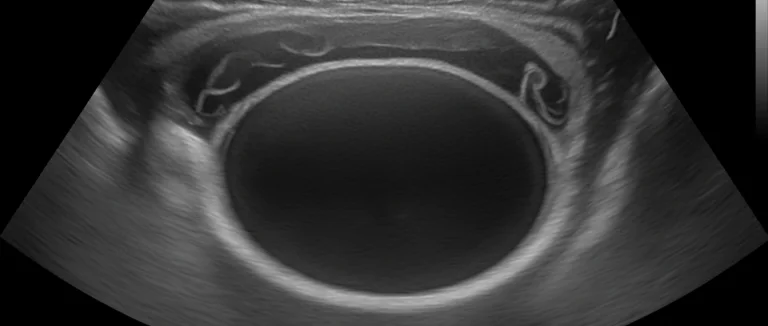

- УЗИ почек и мочевого пузыря — быстрый и безболезненный способ обнаружить камни, опухоли и отёк стенки.